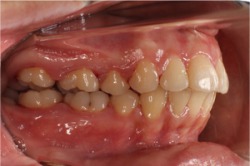

引用元:アイウエオ矯正歯科(https://www.aiueo-kyousei.com/wp/case/database.cgi?cmd=dp&num=326)

前歯が前方に向けて突き出す形で生えていたため、ワイヤー矯正で矯正した症例です。症状に合わせてワイヤーを曲げ、噛み合わせも考えながら矯正されています。